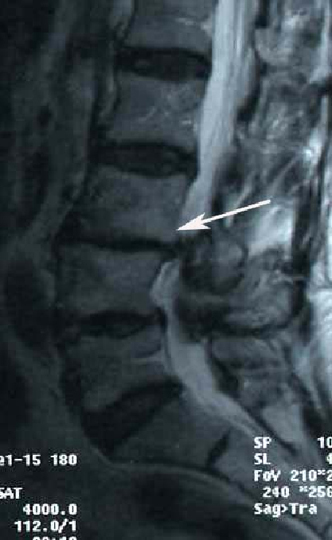

6. Постхирургический спондилолистез

В настоящее время, по данным многих авторов, данный вид листеза считается отдельным видом и развивается вследствие удаления хирургом задних опорных структур позвонка, таких как дужка позвонка или двустороннее удаление фасеточного комплекса при декомпрессивных операциях. Обычно отмечается небольшое смещение позвонка, которое, однако может приводить к интенсивным болям в пояснице и ногах, развивающимся через несколько месяцев после операции.